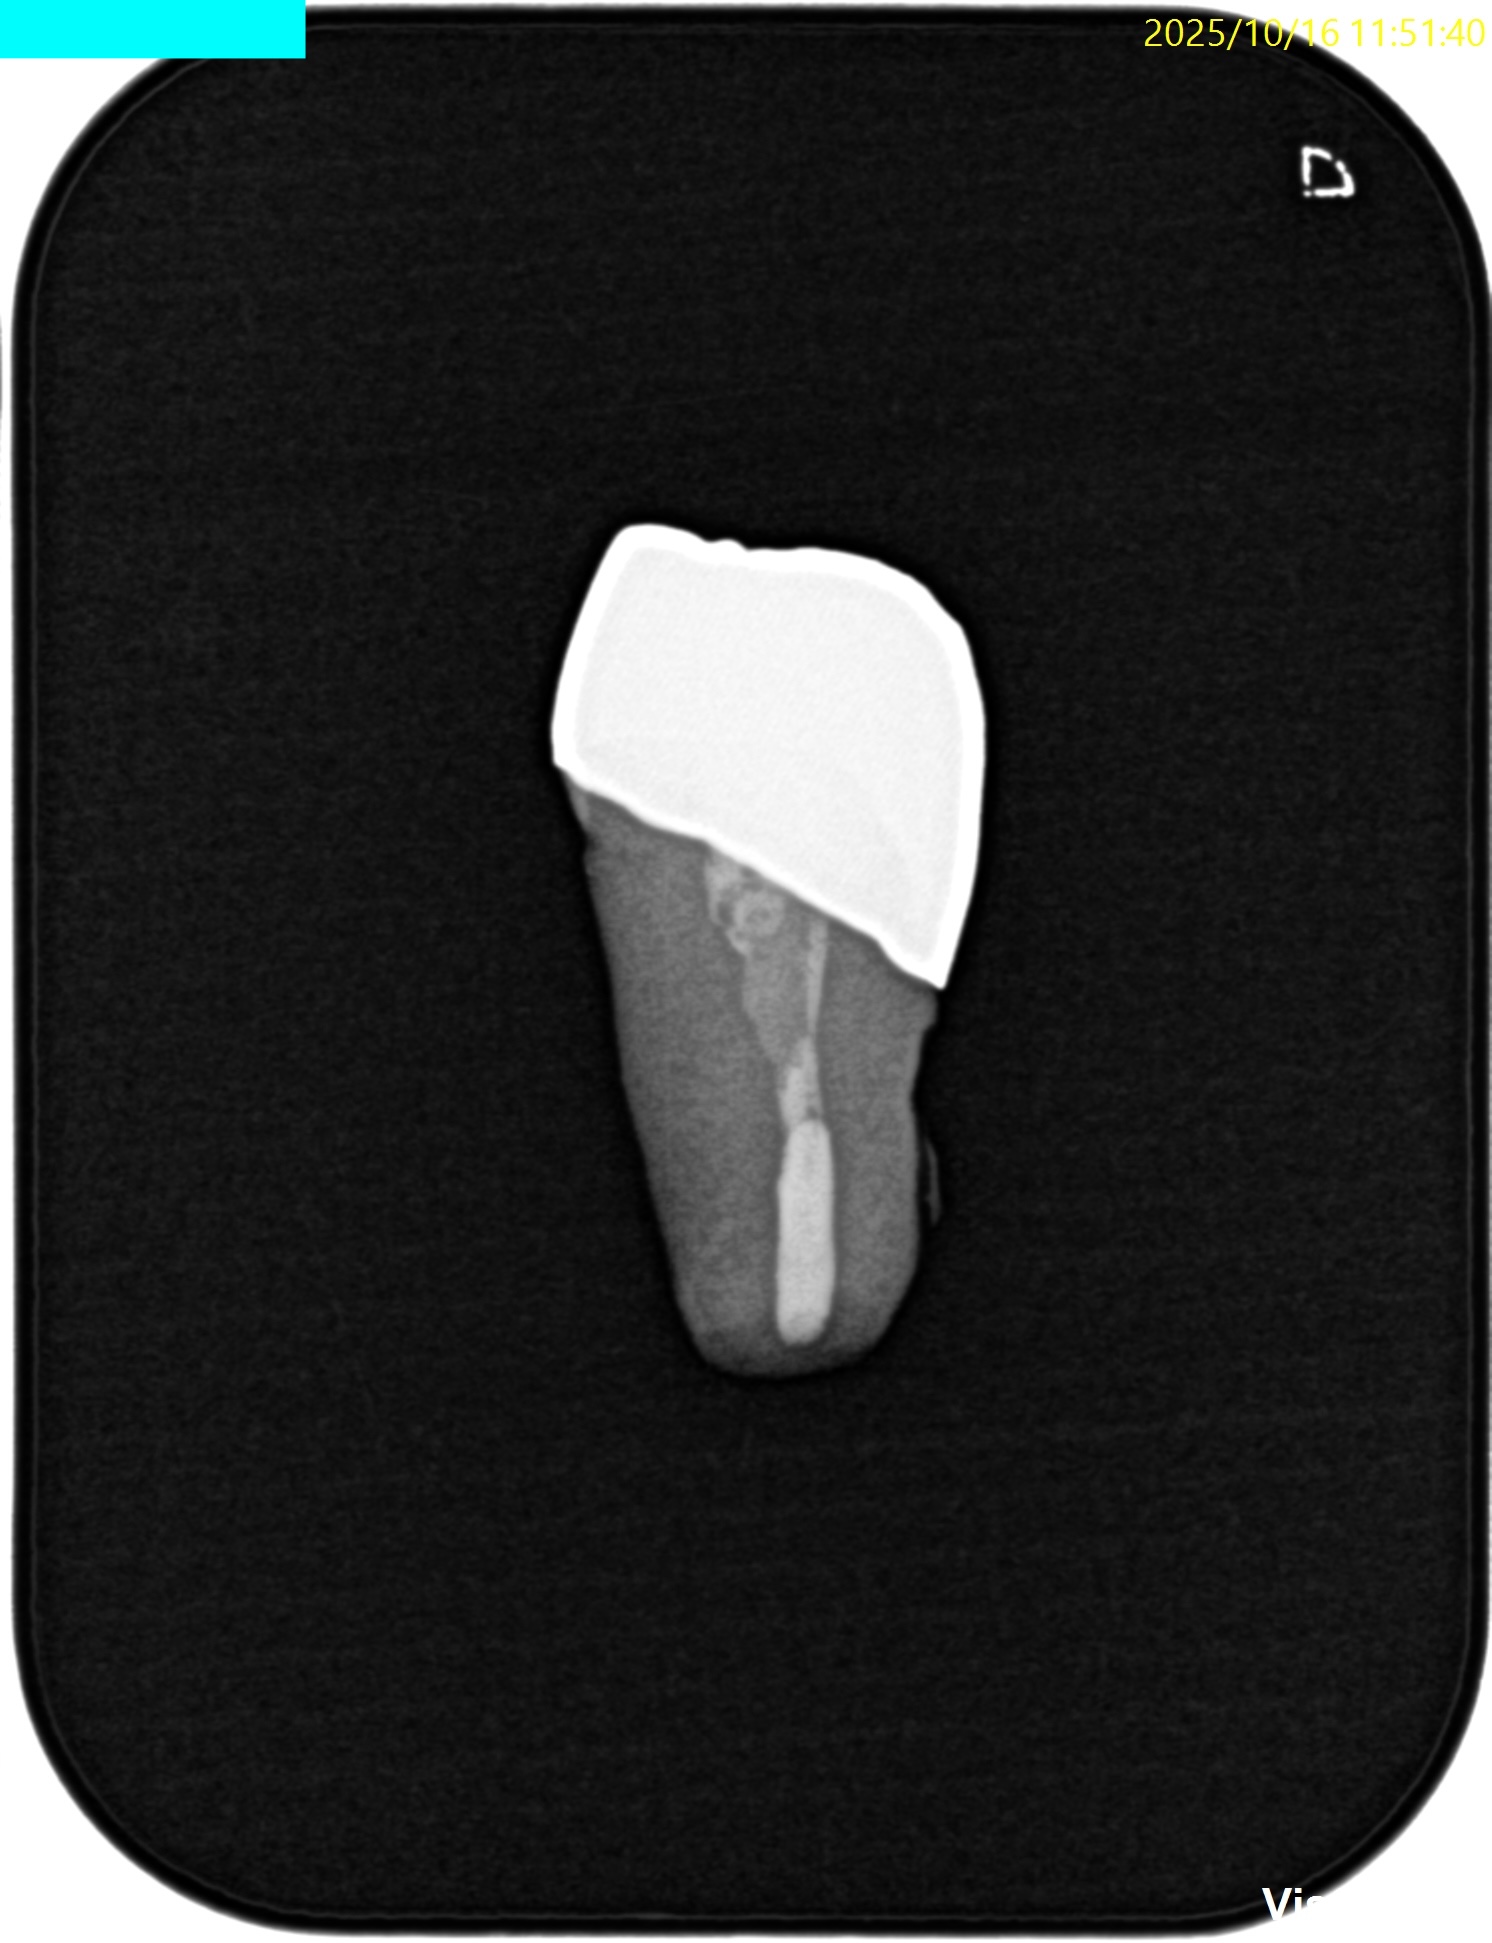

検査とPAは以下である。

またPAではなるほど、歯内療法の問題があるとわかる。

根管充填も根尖部は疎でGutta Percha PointがKink(豚の尻尾)になっている。

根充時にそのポイントよりも先に行かないので他院での治療でそれを押し込めたのだろう。